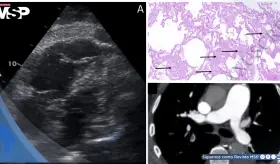

Paciente desarrolló babesiosis severa con shock cardiogénico secundario a miocardiopatía de Takotsubo tras picadura de garrapata en el noreste de Estados Unidos.

El carcinoma de células claras (el tipo más común de cáncer renal) rara vez hace metástasis al corazón, pero cuando ocurre, puede provocar complicaciones mortales como taponamiento cardíaco.